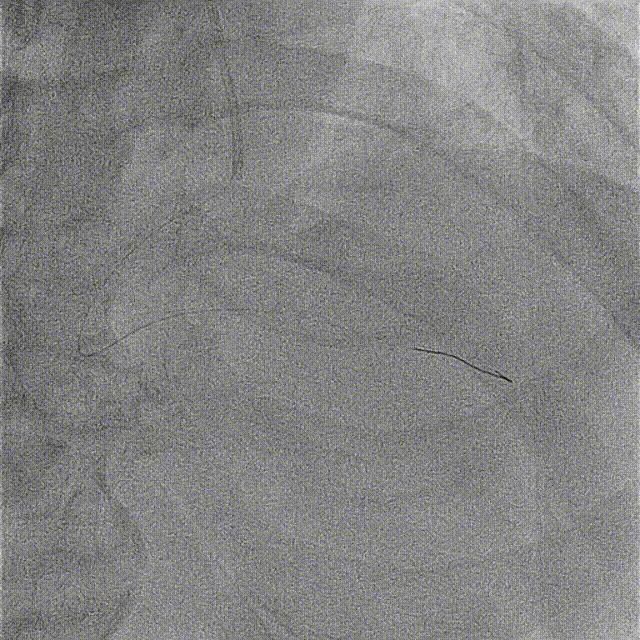

复查造影见右冠血流通畅,无明显残余狭窄及夹层影

远期随访中患者无自觉症状,血压心率稳定。